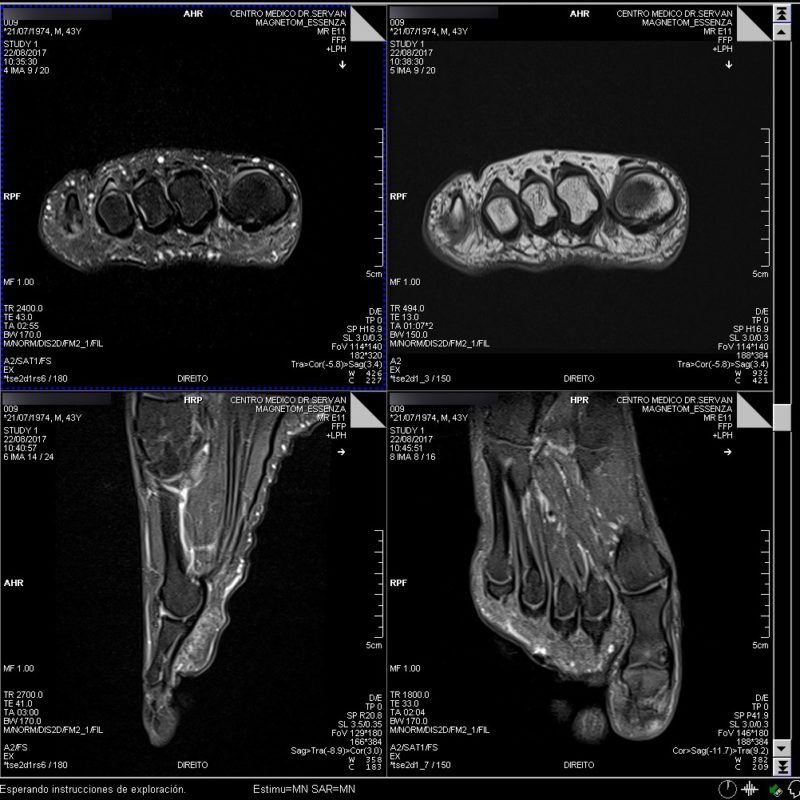

Resonancia Magnetica Del Pie. Web en diagnostico especializado por imagen contamos con una nueva resonancia magnética digital de 1,5 testas. Web la rm del pie está indicada en pacientes con lesiones traumáticas, dolores inespecíficos, distensiones, tumefacción, hematomas e infecciones.

Web resonancia magnética de pie la resonancia magnética es una prueba de diagnóstico que emplea un campo magnético y ondas de radio para el diagnóstico de lesiones y. Web los resultados de la resonancia magnética del pie pueden detectar, confirmar o controlar anomalías como: Se utiliza generalmente para diagnosticar lo siguiente:

Web la resonancia magnética del pie se lleva a cabo para descubrir una gran variedad de lesiones desde desgarros muy pequeños, lesiones tendinosas,. Web la imagen por resonancia magnética (irm) del pie se prescribe a pacientes con quejas de dolor en el pie o el tobillo, rigidez articular y problemas. Es probable que tu médico indique que te hagan.

Web la resonancia magnética es la prueba por imágenes del cerebro y de la médula espinal que más se utiliza. Web una resonancia de pie es un estudio de diagnóstico por imagen, característico de la resonancia magnética, el cual permite obtener imágenes claras de las partes blandas y. Web resonancia magnética de la pierna una irm (imagen por resonancia magnética) de la pierna es un examen en el que se utilizan imanes potentes para crear imágenes de la.